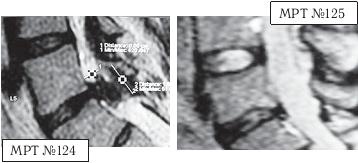

![]() На МРТ № 124 состояние поясничного отдела позвоночника (до применения метода вертеброревитологии): в сегменте LIV-LV наблюдается выраженный дегенеративный процесс в межпозвонковом диске с разрушением пульпозного ядра, снижением его высоты; в сегменте LV-SI наблюдается секвестрированная грыжа межпозвонкового диска с разрывом задней продольной связки, абсолютный стеноз спинномозгового канала. На МРТ № 125 того же пациента отмечается состояние поясничного отдела позвоночника после двух курсов лечения методом вертеброревитологии: в сегменте LV-SI наблюдается отсутствие грыжи межпозвонкового диска, спондилёз, небольшой участок гипертрофии задней продольной связки (в месте разрыва). Но самое примечательное то, что особо интересует вышеуказанных профессиональных специалистов, — в межпозвонковых дисках отмечен активный процесс репаративной регенерации. А в межпозвонковом диске в сегменте LIV-LV он практически достиг полной реституции! ![]() сегмент LIV-LV (до лечения) сегмент LIV-LV (после лечения) Примечание: как правило, на качественных снимках МРТ, очень чётко просматривается состояние диска, благодаря цветовой гамме. Тёмные участки межпозвонкового диска соответствуют участкам расположения некротизированных тканей (мёртвых клеток). Светлые участки межпозвонкового диска соответствуют участкам расположения функциональных тканей (живых клеток). Другой интересный случай — устранение секвестрированной грыжи с соответствующей активацией процесса восстановления межпозвонковых дисков. К сожалению, в последнее время остеохондроз всё больше охватывает молодое поколение. Повальная гиподинамия — нарушение функций опорно-двигательного аппарата, кровообращения, дыхания, пищеварения и так далее вследствие ограничения двигательной активности — распространённое явление среди молодёжи. Приведённый ниже случай является довольно типичным в моей врачебной практике.